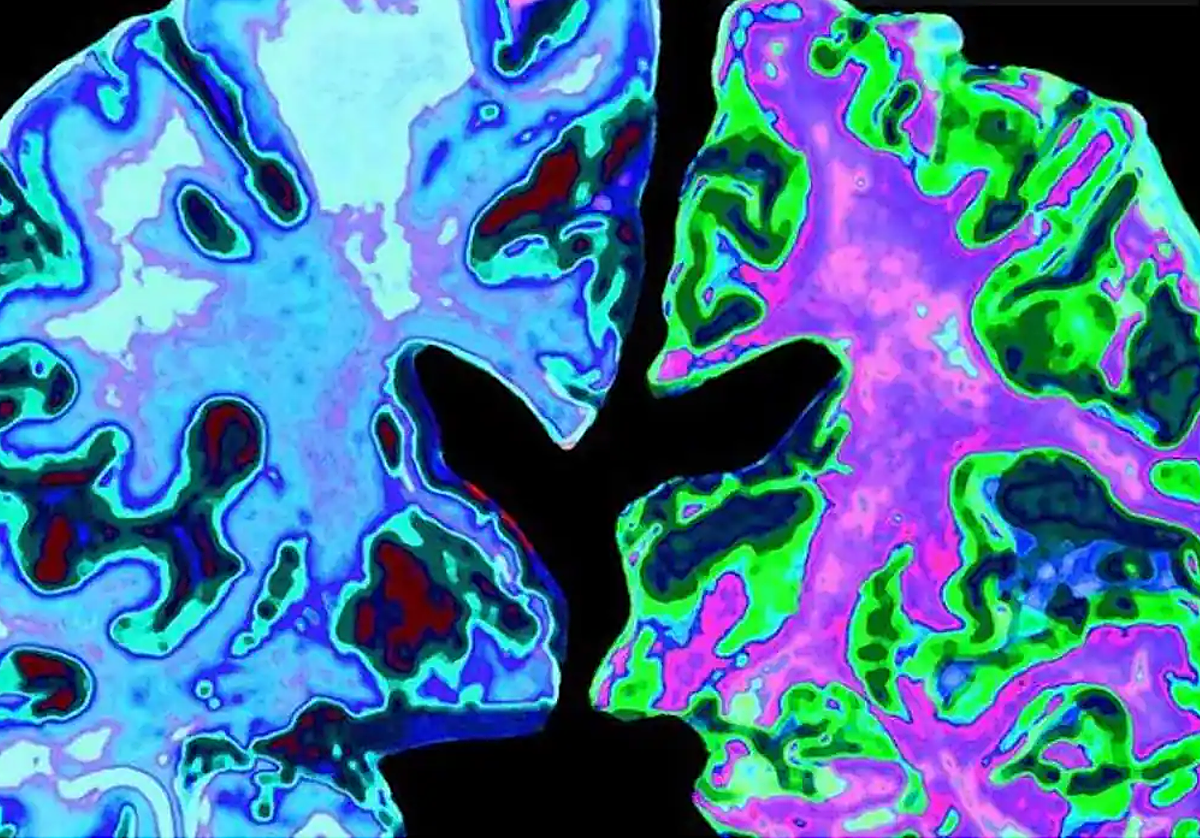

Iniciar sesiónCinco personas que recibieron tratamiento con hormona del crecimiento humano derivada de pituitarias de cadáveres durante la infancia (un tratamiento actualmente prohibido) desarrollaron trastornos tempranos y progresivos en la cognición que cumplían con los criterios diagnósticos de la enfermedad de Alzheimer. Aunque este resultado es ... muy raro, estos hallazgos, publicados en 'Nature Medicine', sugieren que la enfermedad de Alzheimer puede tener formas adquiridas médicamente (iatrogénicas). Sin embargo, no hay evidencia de que pueda transmitirse en otros contextos, como la atención rutinaria o la vida diaria.

Todas las personas descritas en el artículo habían sido tratadas cuando eran niños con un tipo de hormona de crecimiento humano extraída de las glándulas pituitarias de individuos fallecidos (hormona de crecimiento humano derivada de cadáveres o c-hGH). Se utilizó para tratar al menos a 1.848 personas en el Reino Unido entre 1959 y 1985, y se empleó para diversas causas de baja estatura. Fue retirado en 1985 después de que se reconociera que algunos lotes de c-hGH estaban contaminados con priones (proteínas infecciosas) que habían causado la enfermedad de Creutzfeldt-Jakob (CJD) en algunas personas. Posteriormente, la c-hGH fue reemplazada por una hormona de crecimiento sintética que no conllevaba el riesgo de transmitir la ECJ.

Dado que algunas de las glándulas probablemente se obtuvieron de personas que murieron con la enfermedad de Alzheimer, se descubrió que, cuando estas semillas no se eliminaban durante la preparación, algunas personas tratadas con la hormona del crecimiento contaminada desarrollaban más tarde las características clínicas y patológicas de la enfermedad de Alzheimer